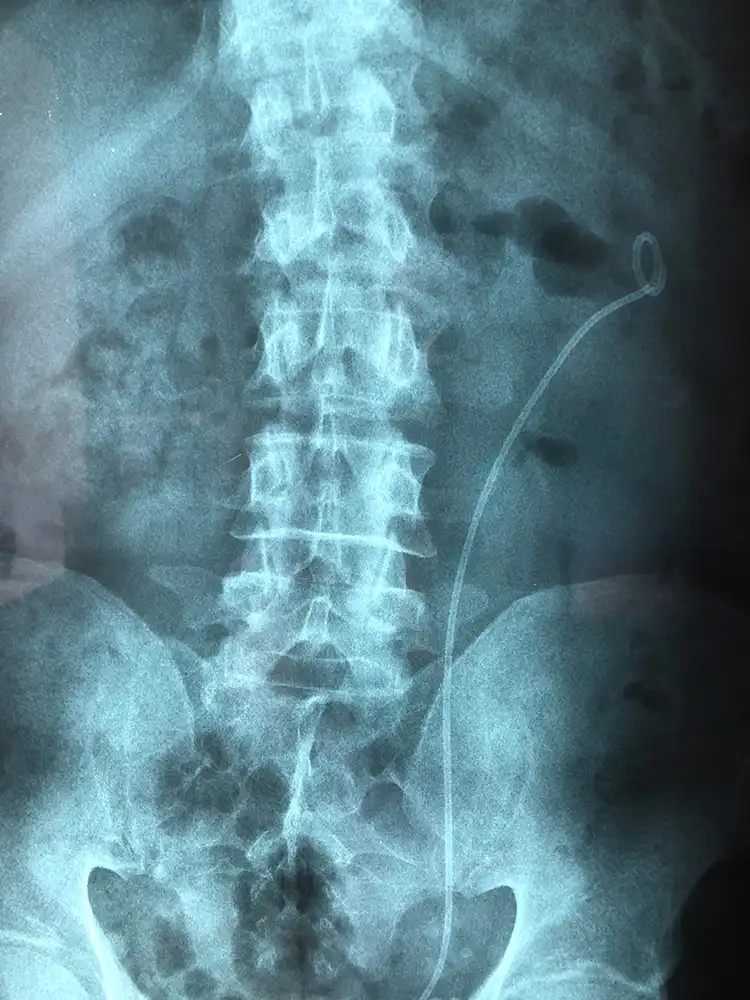

Περιστατικό 1, Ημιάκαμπτη Ουρητηρολιθοθρυψία (semi-rigid URS)

Ασθενής με ευμεγέθη λίθο στο άνω τριτημόριο του αριστερού ουρητήρα, ο οποίος φέρει νεφροστομία λόγω αποφρακτικής ουροπάθειας (Φωτογραφία 1), αντιμετωπίστηκε με laser ουρητηρολιθοθρυψία με ημιάκαμπτο ουρητηροσκόπιο και τοποθέτηση pig-tail με ταυτόχρονη αφαίρεση της νεφροστομίας (Φωτογραφία 2, 1η ημέρα μετεγχειρητικά). Η τρίτη φωτογραφία είναι στις 15 ημέρες πριν την αφαίρεση του pig-tail.